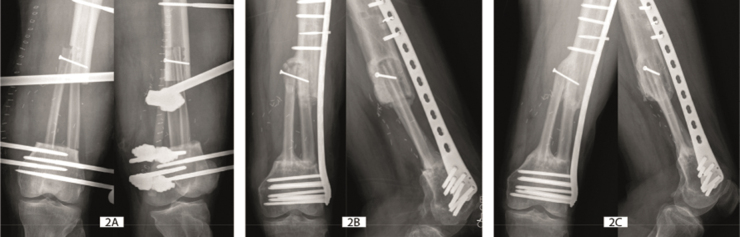

Results: When bony consolidation of the 33 cases were examined in detail, 4 different modes of flap hypertrophy were defined: type 0- absence of hypertrophy, type 1- limited hypertrophy, type 2- marked hypertrophy triggered by stress fracture, and type 3- massive hypertrophy enhanced by peripheral bone production.